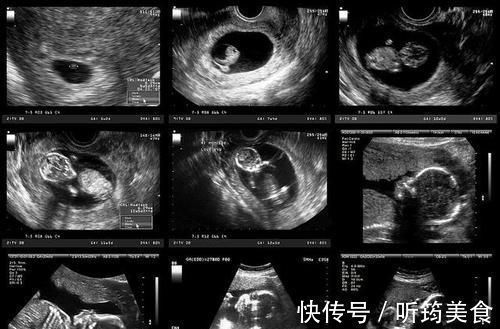

然而,由于技术上的限制,该算法尚未完善,因此,最终的成像结果也达不到清晰可见的程度,医生在诊断时,大部分判断依靠专业知识,而剩下的只能靠经验以及感觉。

文章插图